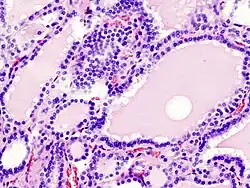

.jpg)

Klinisch: Hyperthyreose